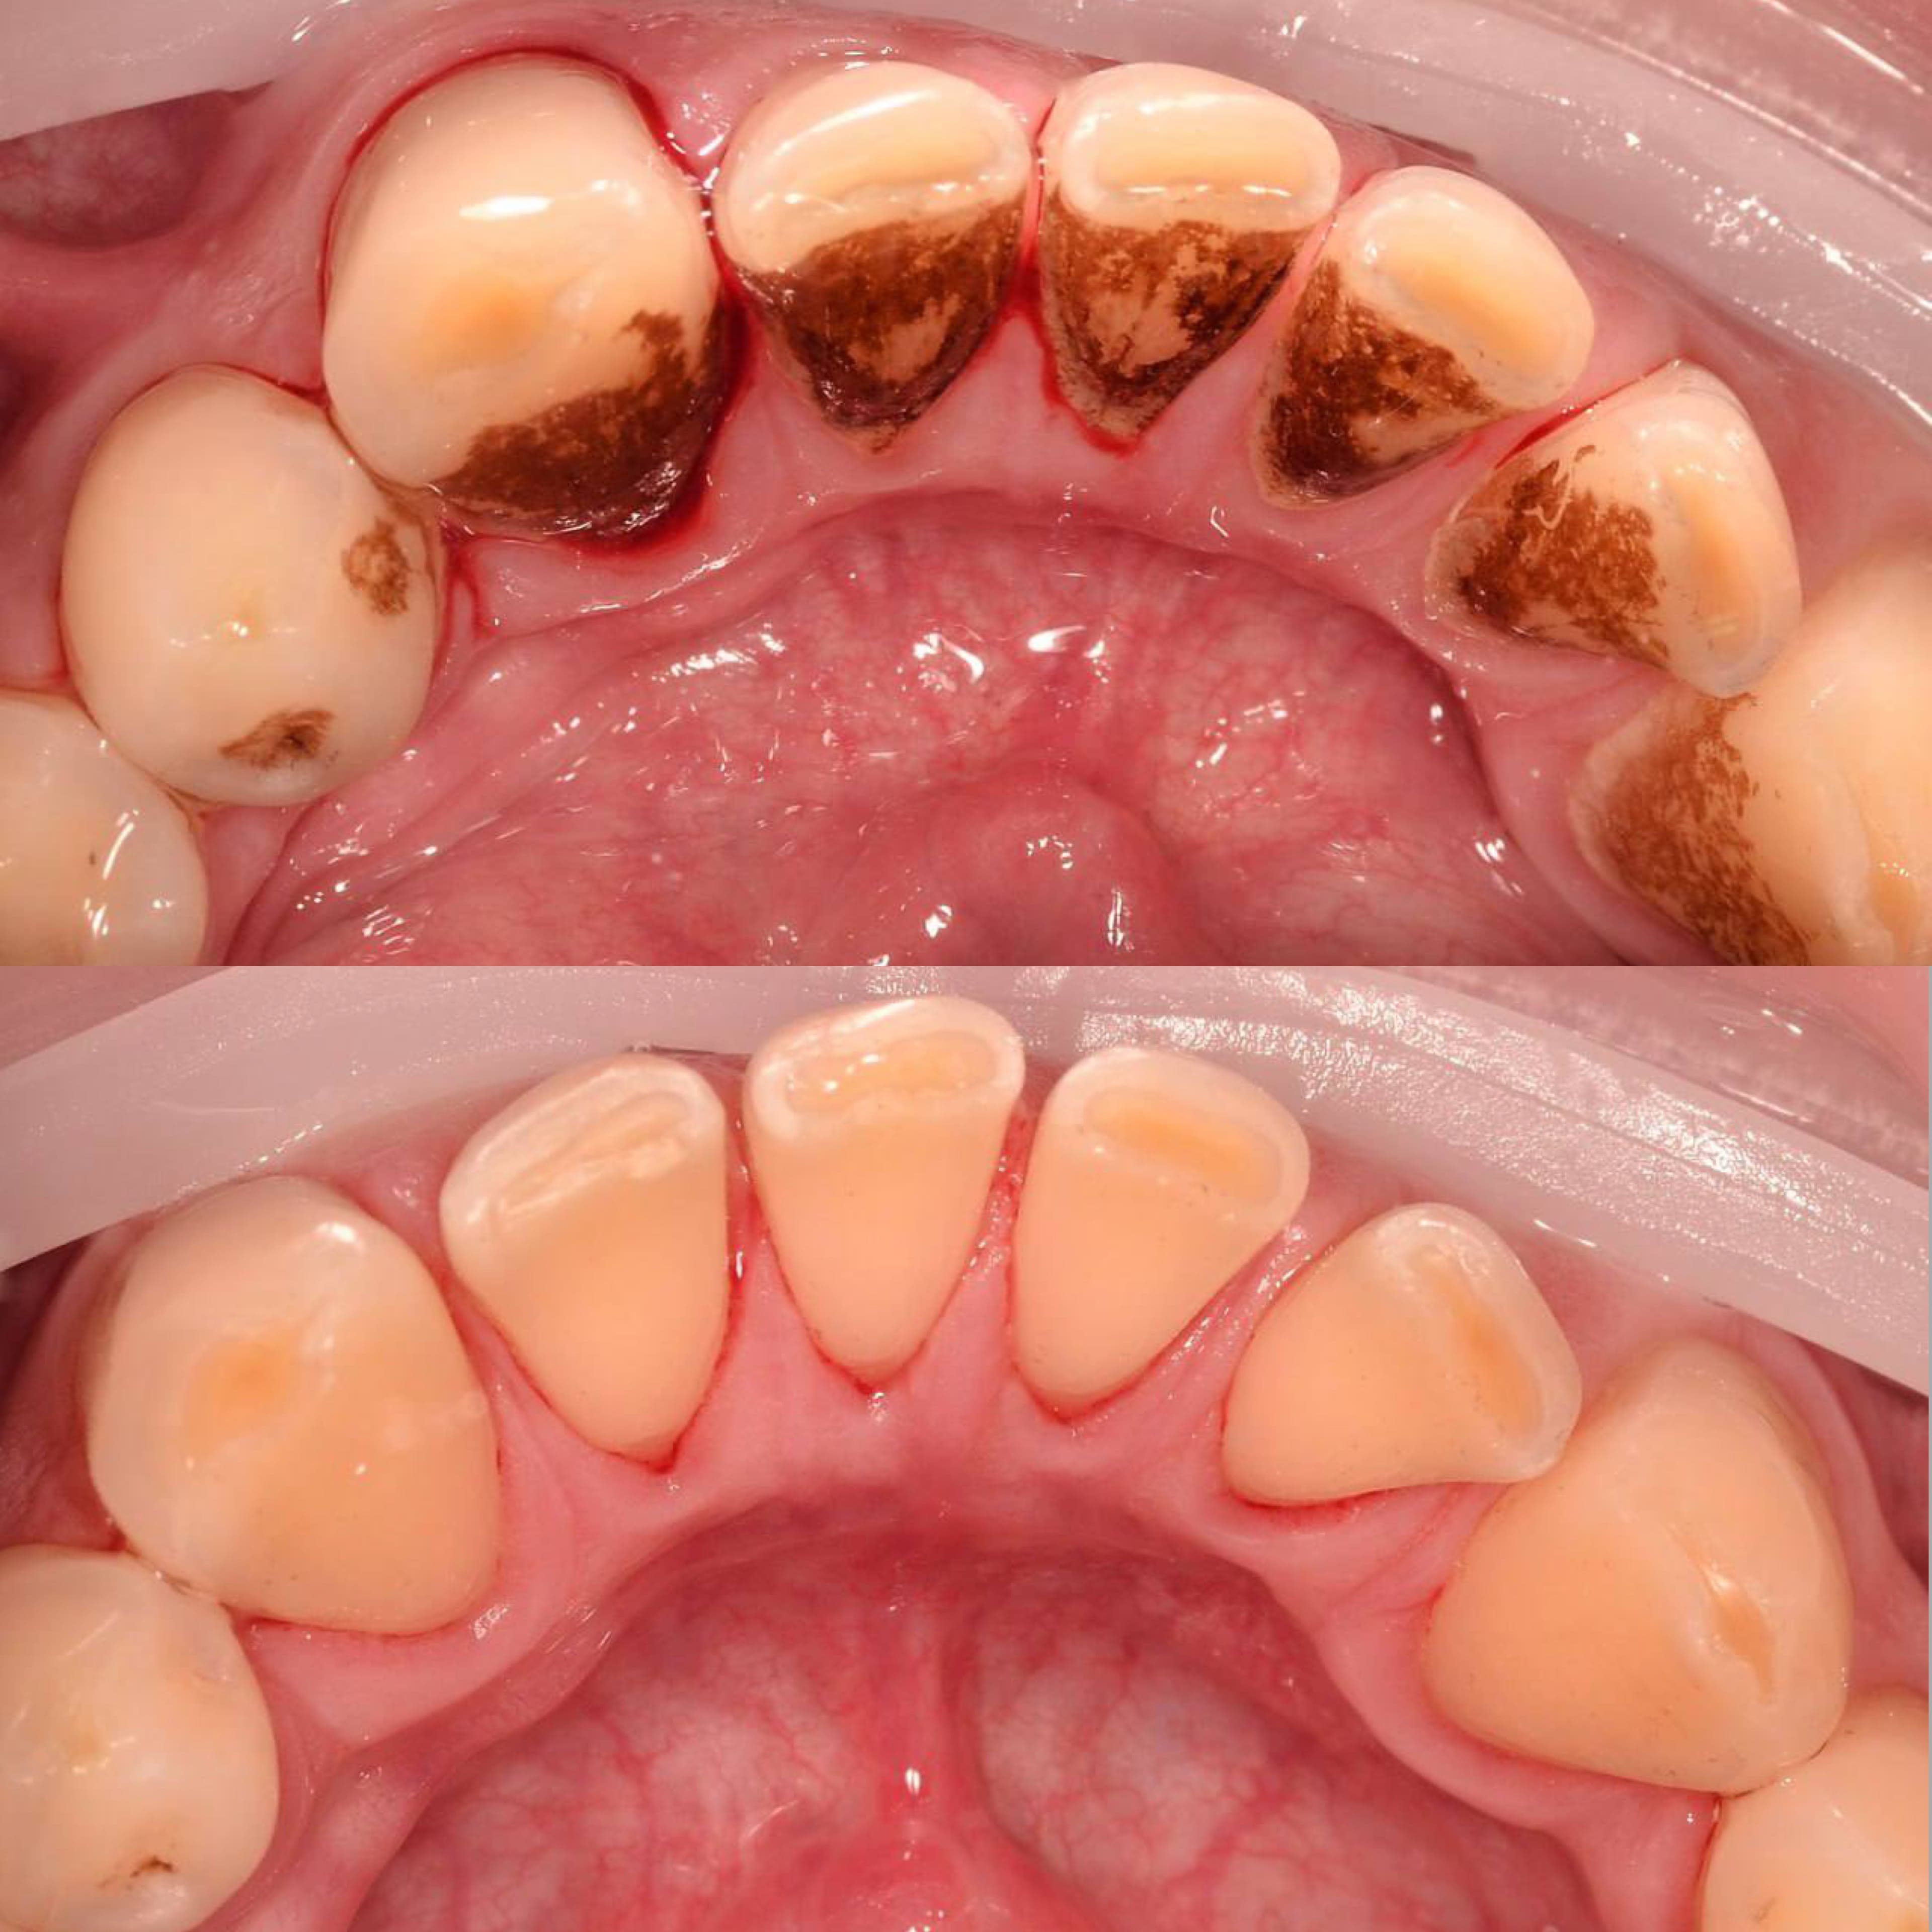

Даже если вы хорошо чистите зубы дома, на зубах со временем скапливается налет. А также на зубах есть труднодоступные места, которое вы не прочищаете. Поэтому нужно приходить на профгигиену в клинику не реже 1 раза в 6 месяцев. Очищение налета, удаление зубного камня, укрепление эмали — все это профессиональная гигиена. На сегодня это лучший способ защитить зубы от кариеса и сохранить десны здоровыми.

Процесс включает несколько этапов:

• Удаление зубного камня с помощью ультразвука;

• Очистка труднодоступных участков с использованием порошкового оборудования Air Flow;

• Полировка зубов специальными пастами, придающими эмали гладкость и блеск;

• Завершение процедуры нанесением реминерализующего состава для укрепления зубов.

• обучение домашней гигиене и подбор средств.